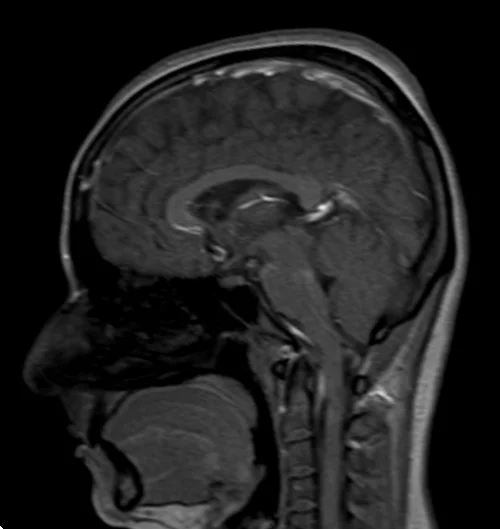

brain mri localizer image